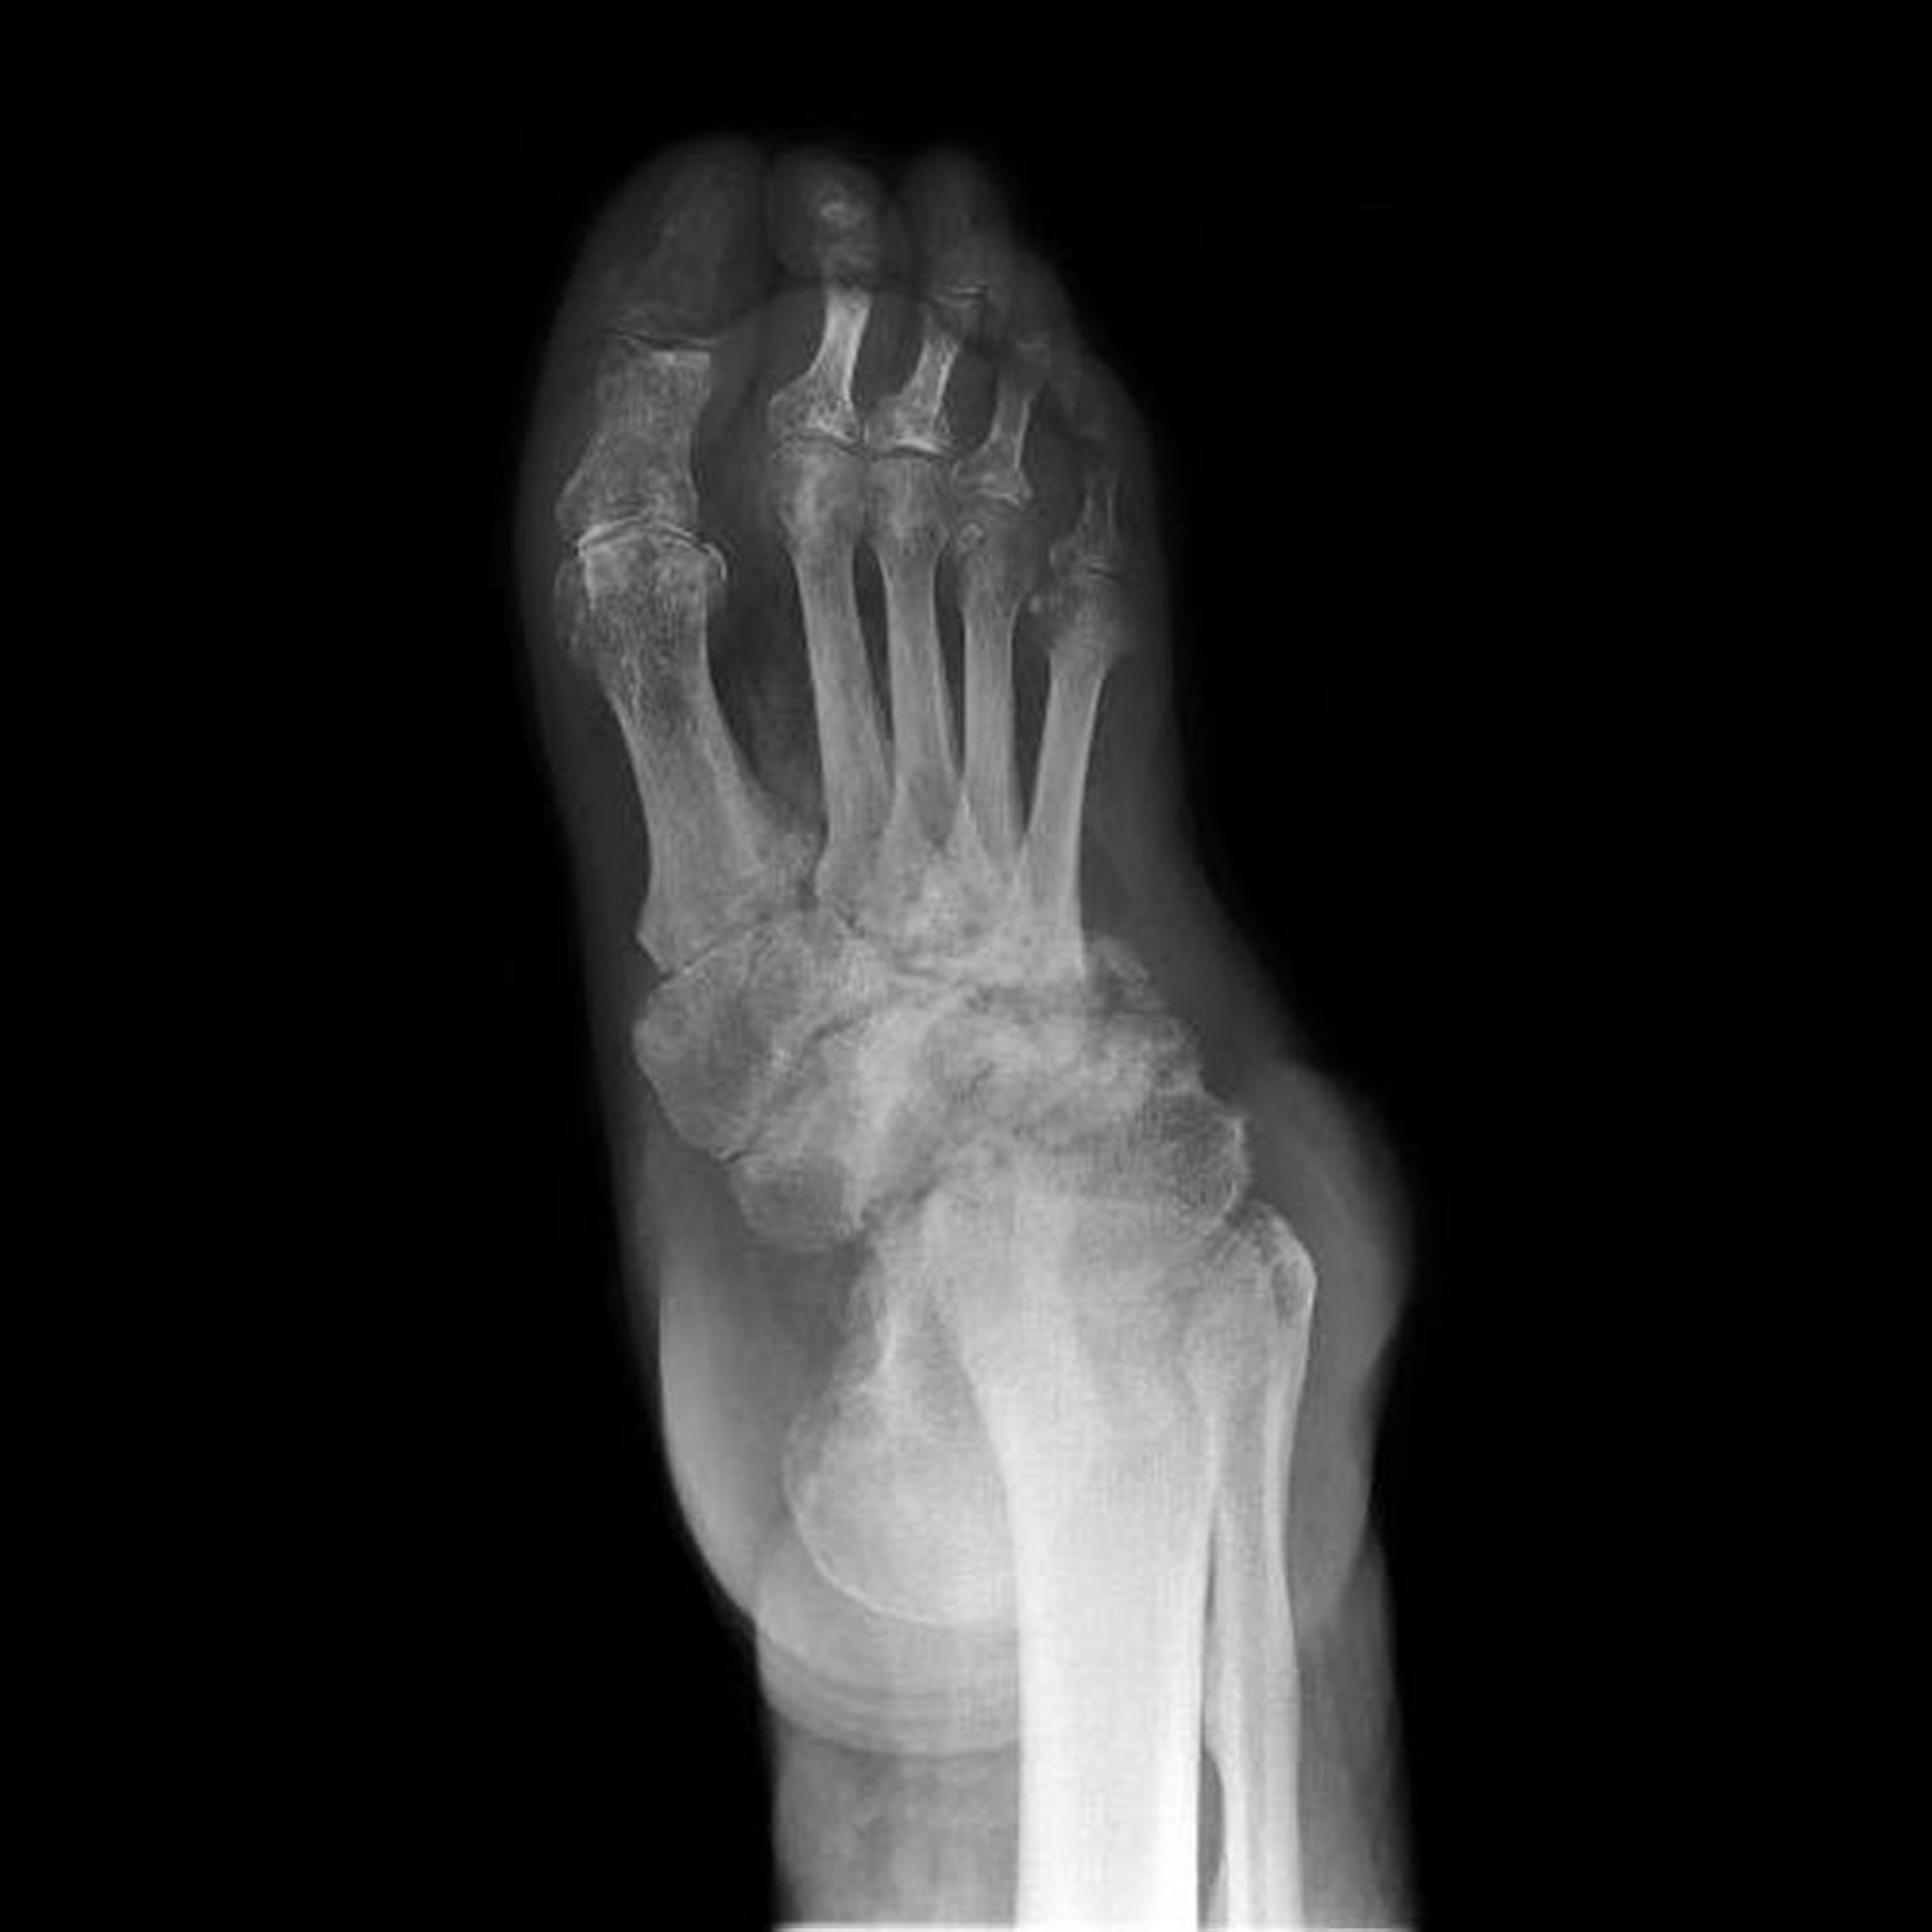

早期の神経病性関節症におけるX線上の異常は,変形性関節症における異常と類似していることが多い(変形性関節症の診断を参照)。進行後期にみられる主要な徴候は以下のものである:

• 骨の断片化

• 骨破壊

• 新たな骨増殖

• 関節裂隙の狭小化

関節液貯留および関節の亜脱臼がみられることもある。骨が変形することがあり,また皮質に隣接して新たな骨が形成される(関節包内に始まり,しばしば骨幹[特に長管骨]に進展する)。まれに,軟部組織で石灰化および骨化が起こる。異様な形状の大きな骨棘が関節縁または関節内にみられることがある。弯曲した大きな(オウムの嘴)骨棘が,臨床的な脊椎疾患なしに,脊椎にしばしば発症する。